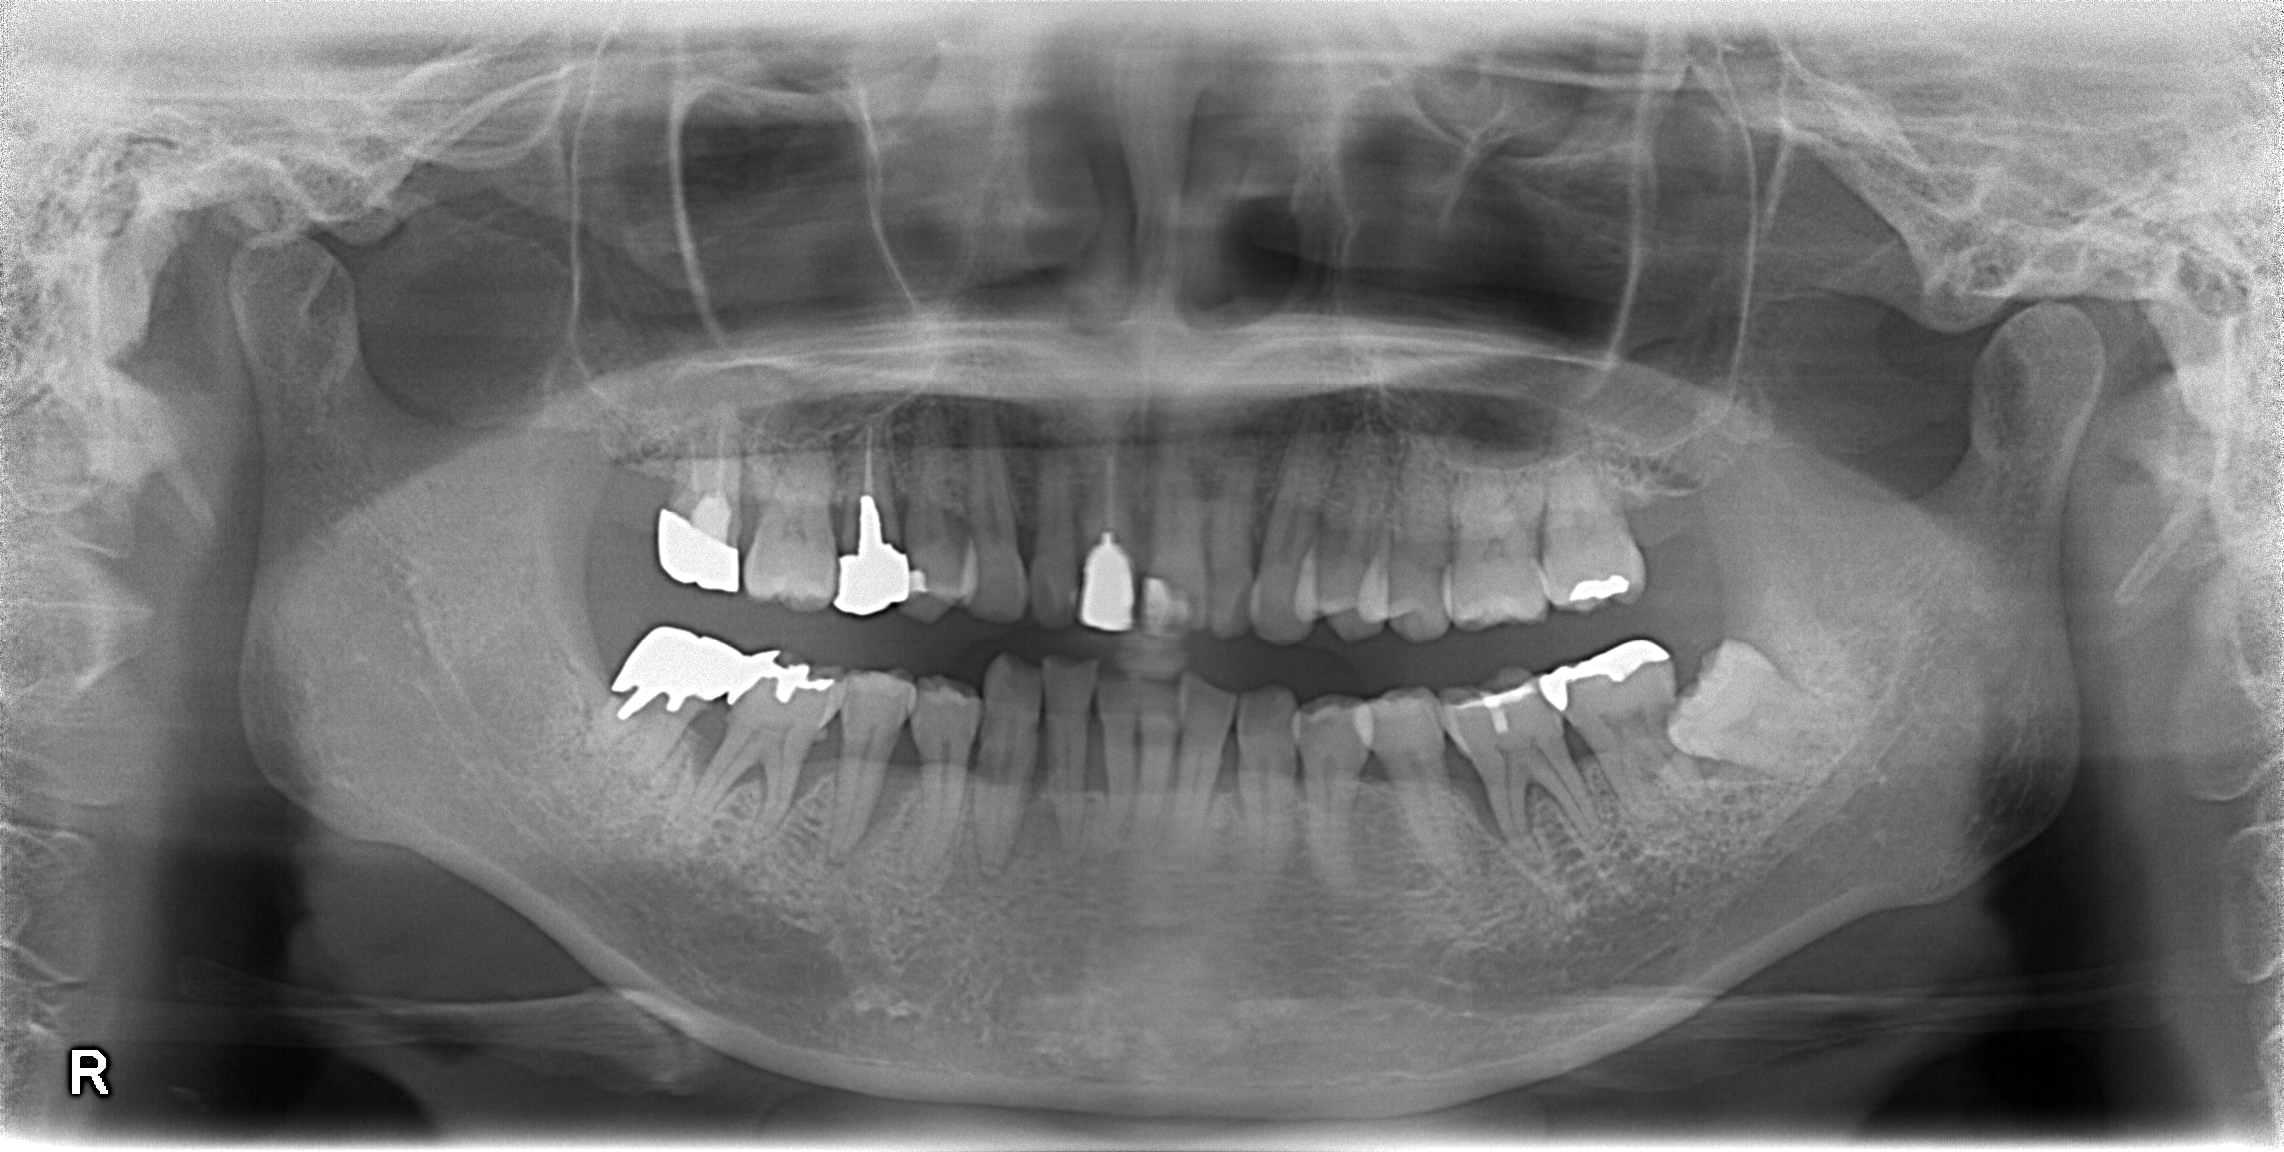

3年程度当院で歯周病のコントロールを行っている患者さんです。

さて、今回の場合は

一通りの歯石の除去

プラークコントロールの徹底(歯磨きの徹底)

を行った後、1ヶ月に1回の定期検診をずっと行って歯周病の進行を遅らせていました。

しかし、最近になって下の前歯がぐらぐらと動き始めました。